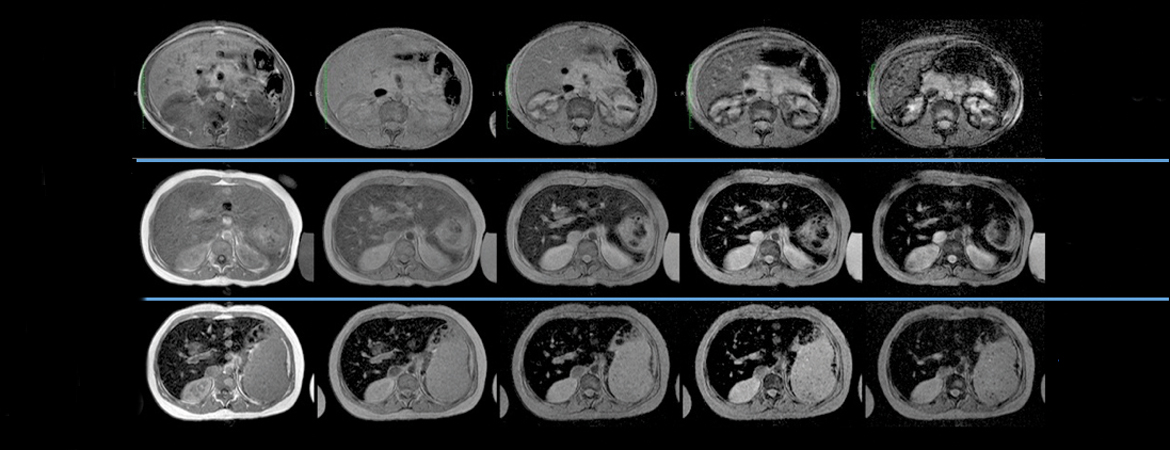

Axel Rüfer, Christine Bapst, Rudolf Benz, Jens Bremerich, Nathan Cantoni, Laura Infanti, Kaveh Samii, Mathias Schmid, Jean-Paul Vallée (Author) Role of liver magnetic resonance imaging in hyperferritinaemia and the diagnosis of iron overload Fulltext PDF Fulltext HTML